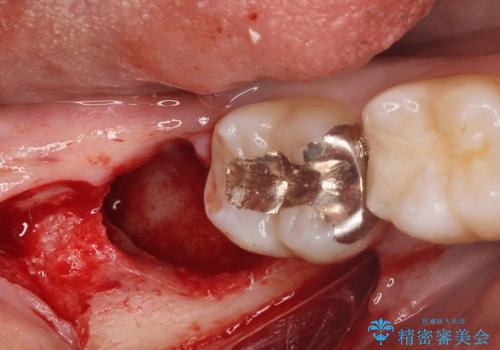

親知らずを長年放置すると、手前の歯が虫歯になるリスクが上がります。

そのようになる前に抜歯することをお勧めします。